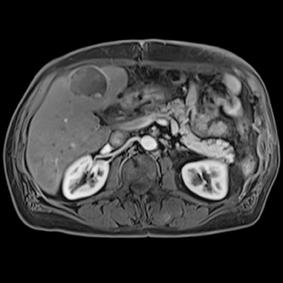

This series of images taken with TwistVibe show how the new technology enables radiologists to catch the correct time point of lesion enhancement within the arterial phase. With TWIST-VIBE, it is now possible to generate multiple stacks of images from the arterial phase to follow the lesion enhancement over time. With that, other so-far-unseen lesions may become visible. Images courtesy of University Hospital IKRN, Mannheim, Germany.

As MRI popularity increases, manufacturers are exploring novel ways to use the equipment in areas such as abdominal imaging, which has generally been dominated by computed tomography (CT). “We believe that MR is actually a better tool for detecting small lesions because of its improved contrast-to-noise ratio. We’ve been spending a lot of time making abdominal images easy and faster for patients and technologists,” said Clarkson. “There are some new sequences that Siemens showed at RSNA that allow patients to free breathe, and we can still get exquisite details of particularly the liver, which is a major organ for oncology imaging,” he explained. The Freezeit application, which received U.S. Food and Drug Administration (FDA) approval in November 2013, is available with the StarVibe and TwistVibe sequences. The StarVibe sequence is designed to enable free-breathing, contrast-enhanced liver imaging, and the TwistVibe sequence is designed to enable correct contrast imaging in dynamic liver MRI for all patients and lesions. Freezeit is currently available on the Aera wide-bore 1.5 Tesla and Skyra wide-bore 3.0 Tesla systems.